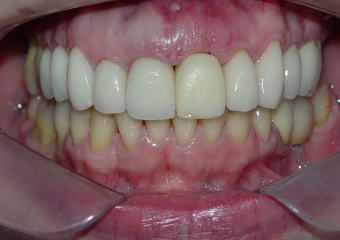

Sorriso inicial